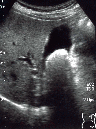

結石

右肋間走査